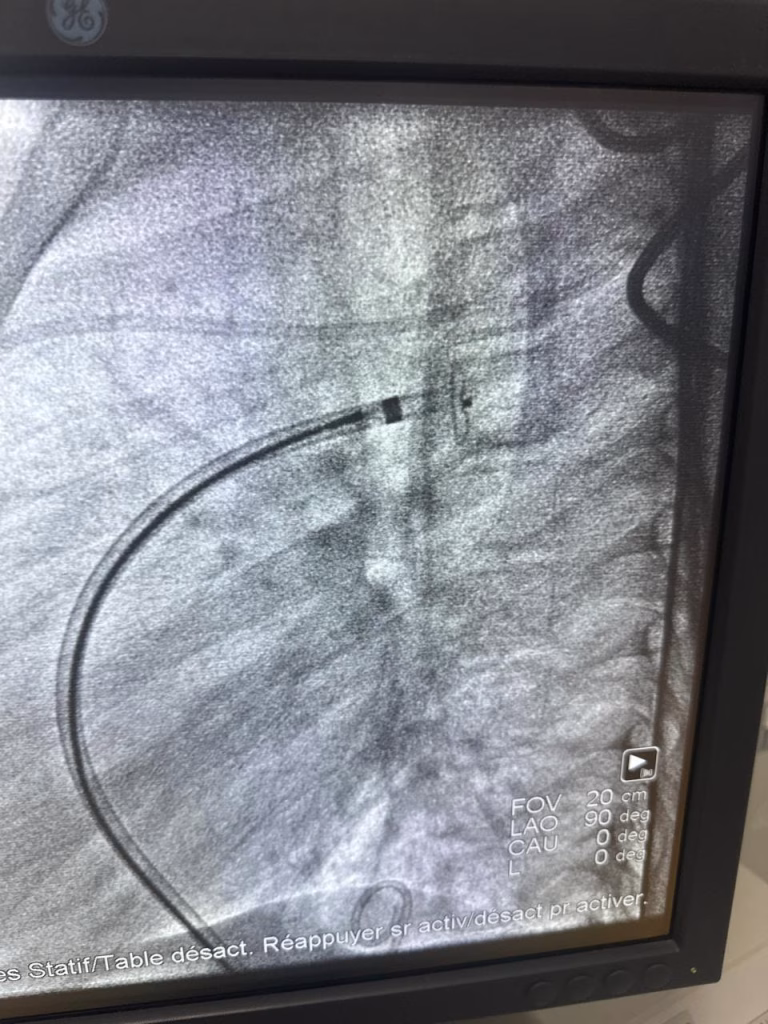

في إطار تعزيز التعاون الدولي في المجال الصحي، نظم المركز الاستشفائي الجامعي محمد السادس بوجدة، القافلة الطبية الثانية المتخصصة في قسطرة القلب التداخلية للأطفال المصابين بتشوهات خلقية في القلب. جرت هذه الحملة يومي 26 و27 دجنبر 2025، بشراكة مع جهة الشرق الكبير بفرنسا (Grand Est) ومكتب الشرق الكبير للتضامن والتعاون من أجل التنمية (GESCOD).

ستفاد من هذه المبادرة ثلاثة أطفال، تم علاجهم باستخدام أحدث التقنيات الطبية المتقدمة والمعترف بها عالمياً. وتؤكد المصادر الطبية أن حالتهم الصحية جيدة وفي تحسن مستمر، مما يعكس نجاح الإجراءات التداخلية التي تجنب الجراحة المفتوحة التقليدية.

تشكل التشوهات الخلقية في القلب أحد أبرز التحديات الصحية لدى الأطفال، حيث يولد حوالي 1% من المواليد بهذه العيوب، مثل الثقوب بين الحجرات أو تضيق الصمامات. تعتبر القسطرة التداخلية الخيار الأمثل في كثير من الحالات، إذ تتم عبر إدخال أنبوب رفيع (قسطرة) من خلال الأوعية الدموية، غالباً من الفخذ، لإصلاح الخلل دون شق جراحي كبير. هذه التقنية أقل خطراً، تقلل من وقت التعافي، وتحقق نسب نجاح تفوق 90% في معظم الحالات.

لم تقتصر القافلة على العلاج فقط، بل شملت حصصاً تكوينية مكثفة لأطباء مصلحة طب الأطفال بالمركز، تحت إشراف أستاذ مغربي خبير في هذه التقنية. يهدف ذلك إلى نقل الخبرات وتعزيز القدرات المحلية، تمهيداً لتحقيق الاستقلالية الكاملة للفرق الطبية المغربية في إجراء مثل هذه العمليات.